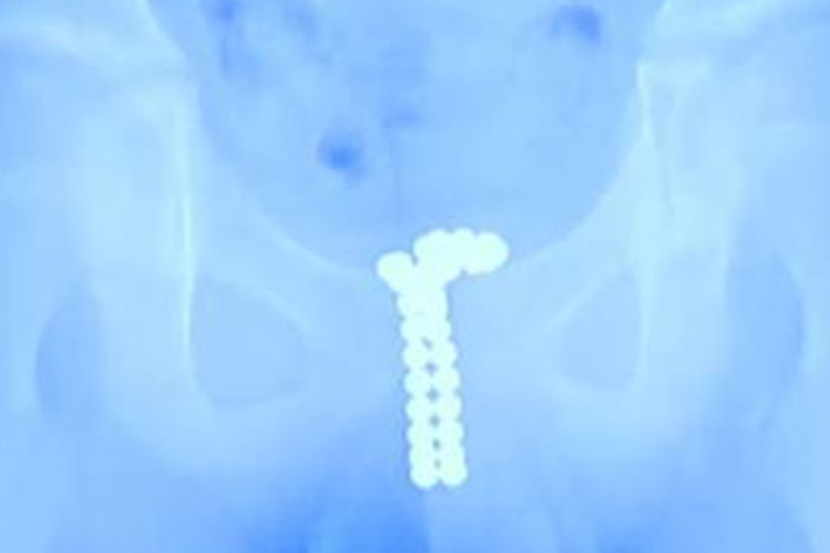

Imbasan Sinar-X menunjukkan terdapat sejumlah bola kecil magnetik di dalam kemaluan seorang budak lelaki berusia 12 tahun.

Imbasan Sinar-X menunjukkan terdapat deretan bola kecil magnetik seperti bentuk 'U'.